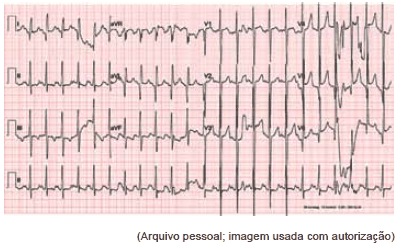

O seguinte eletrocardiograma de um menino de nove meses é compatível com qual cardiopatia congênita?

Paciente foi transferido de urgência em vaga zero de UBS para pronto-socorro cardiológico sem história de cardiopatia congênita prévia. Mãe refere que nasceu sem intercorrências, de parto normal, e teve alta no segundo dia de vida. Notou que sua criança tinha dificuldades às mamadas e ficava roxo aos esforços. Após exame físico e cuidados imediatos de intubação orotraqueal, cateter venoso central e sonda nasogástrica, foram feitos os seguintes exames:

Qual é o diagnóstico mais provável?